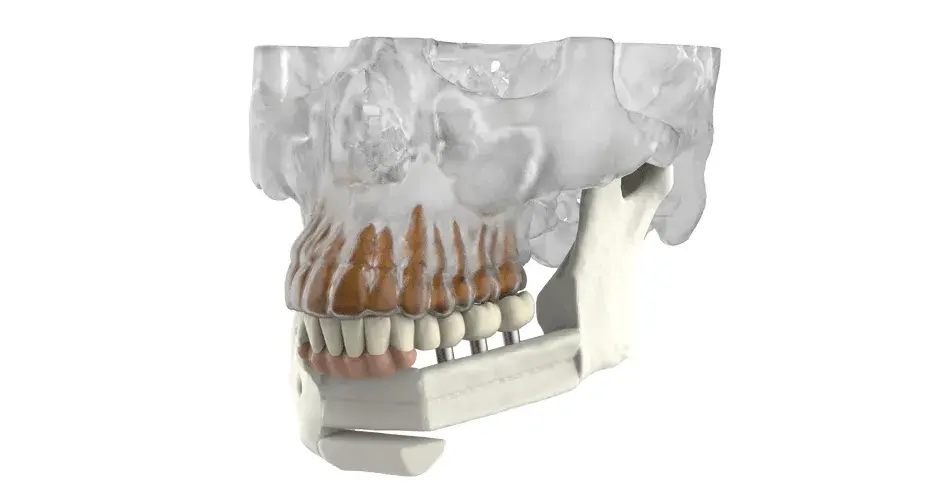

3D Systems' VSP® surgical planning solutions for craniomaxillofacial (CMF) applications received FDA clearance as a service-based approach to personalized surgery over 10 years ago.

3D Systems and Stryker Corporation have partnered to provide surgeons with best-in-class products and services for craniomaxillofacial surgeries. As a leader in personalized healthcare solutions, 3D Systems has planned and delivered devices for more than 140,000 patient-specific cases. The Stryker Craniomaxillofacial business specializes in providing patient-specific options and innovative solutions that help drive efficiencies in surgical suites. The combination of Stryker’s specialized team and advanced implants with 3D Systems' cutting-edge 3D printing technologies and expert consulting services positions both companies to provide a superior level of service to healthcare professionals who use these revolutionary solutions.